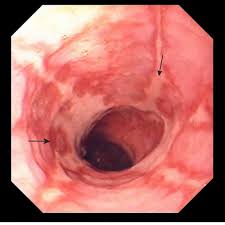

위내시경검사를 통해 위식도 접합부 염증여부를 확인하고 위식도 역류에 의한 식도 점막 손상이 있는지를 확인하고 역류성식도염을 진단할 수 있다고 한다.

위내시경검사는 특수 카메라가 달린 내시경을 입을 통해 삽입한 후 식도부터 위까지 실시간으로 모니터를 보면서 병변 유무를 확인할 수 있다고 한다. 위내시경검사를 통해 역류성식도염 뿐 아니라 식도암, 위염, 위암 등의 질환을 진단할 수 있다고 한다.